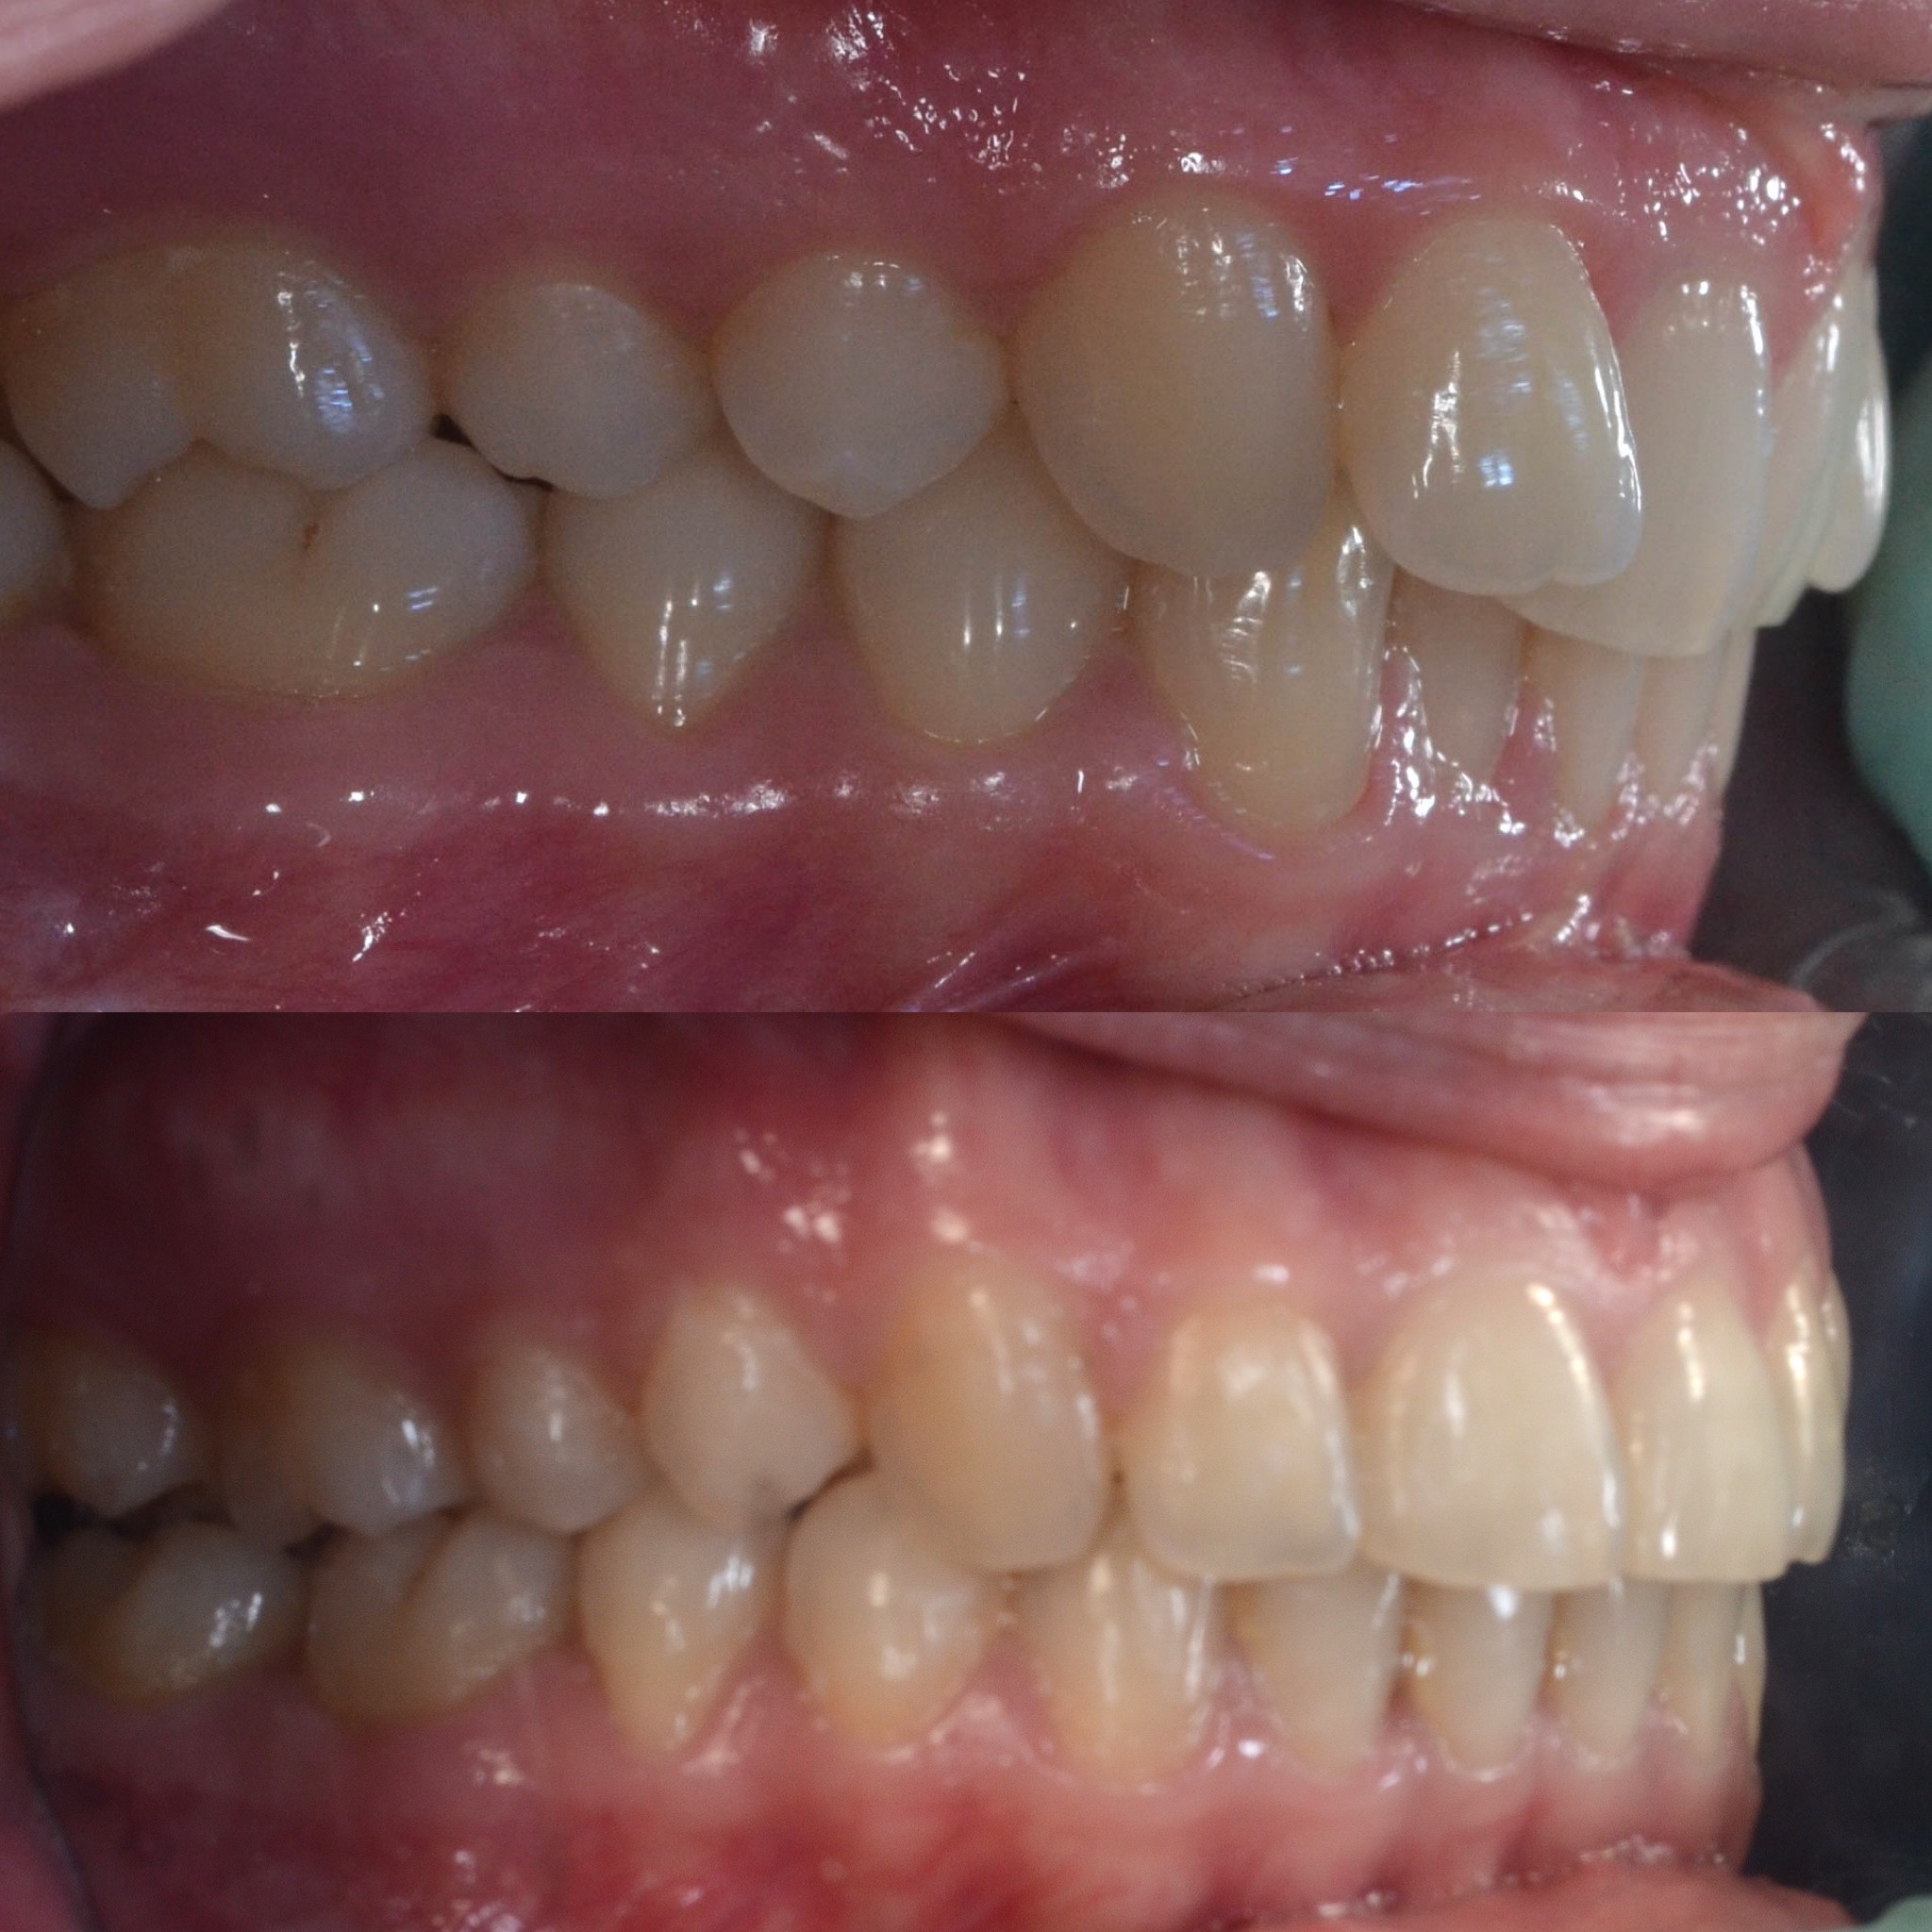

U galeriji slika su prikazani klinički slučajevi ovakvih odraslih pacijenta bilo da se radi samo o ortodontskoj terapiji ili predprotetskoj ortodonciji.

Na sljedećoj slici se mogu vidjeti početak i kraj ortodontske i protetske terapije. Protetske radove radio je dr. Goran Radica.

Na sljedećoj slici mogu se vidjeti početak i kraj ortodontske terapije. Pacijentica je upućena od svog stomatologa nakon što nije bila zadovoljna izgledom osmjeha i odnosom zuba i gingive u privremenom protetskom radu. Napravljena je ortodontska terapija samo u gornjoj čeljusti a nakon toga novi privremeni protetski rad.